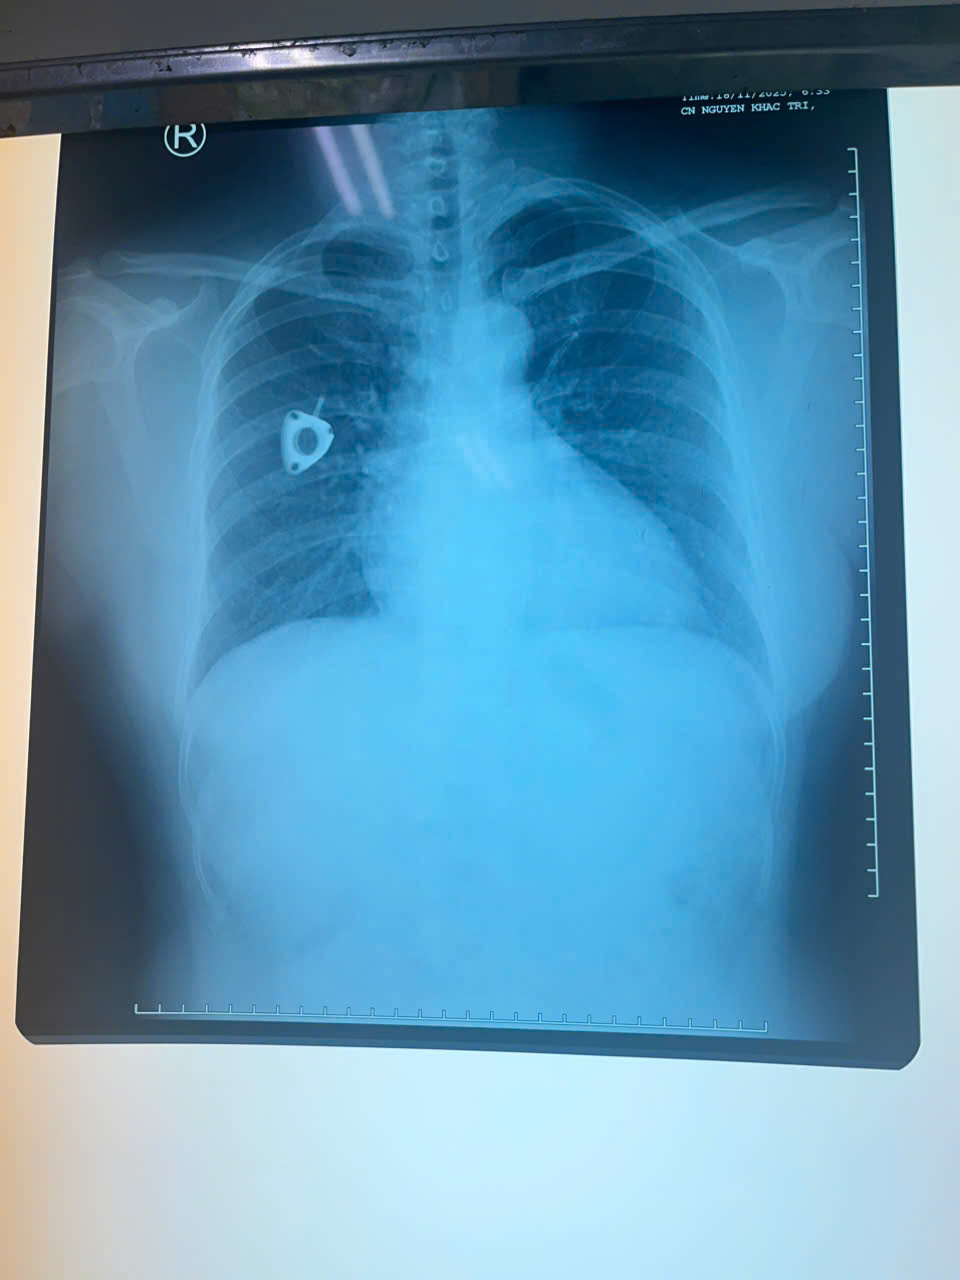

Mới đây, bệnh nhân đi khám tầm soát và chụp CT ngực tại một cơ sở y tế tư nhân thì phát hiện dị vật trong tim, nằm vắt ngang tại vị trí động mạch phổi hai bên. Sau đó, bệnh nhân quay về bệnh viện đã điều trị ung thư trực tràng để tiếp tục thăm khám và được tiến hành chụp X-quang ngực.

Kết quả ghi nhận mất liên tục thân catheter, xác định catheter đã bị đứt. Phần buồng truyền dưới da vẫn còn tại vị trí dưới xương đòn phải, phần đầu còn lại đã di chuyển về tim và nằm trong động mạch phổi.

Bệnh nhân được chỉ định rạch lấy phần catheter còn lại dưới da tại vị trí đặt port. Sau khi rạch, bác sĩ rút được phần catheter gần nhưng không thể rút được đoạn xa vì đã trôi sâu vào buồng tim di chuyển đến động mạch phổi. Sau đó, bệnh nhân được tư vấn đến Bệnh viện Quân y 175 để xử trí chuyên sâu.